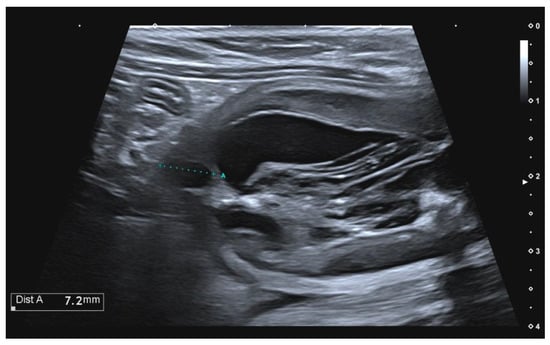

A vesicourachal diverticulum was observed in three out of ten cats (Table 2). In two subjects, the vesicourachal diverticula were intramural (Figure 2), and in one cat, the vesicourachal diverticulum was extramural.

Figure 2. Longitudinal ultrasound image of the urinary bladder in a cat, showing the presence of a small, fluid-filled, anechoic structure, in the cranial bladder wall, showed by the cursor indicated with the letter “A”, consistent with intramural vesicourachal diverticulum.